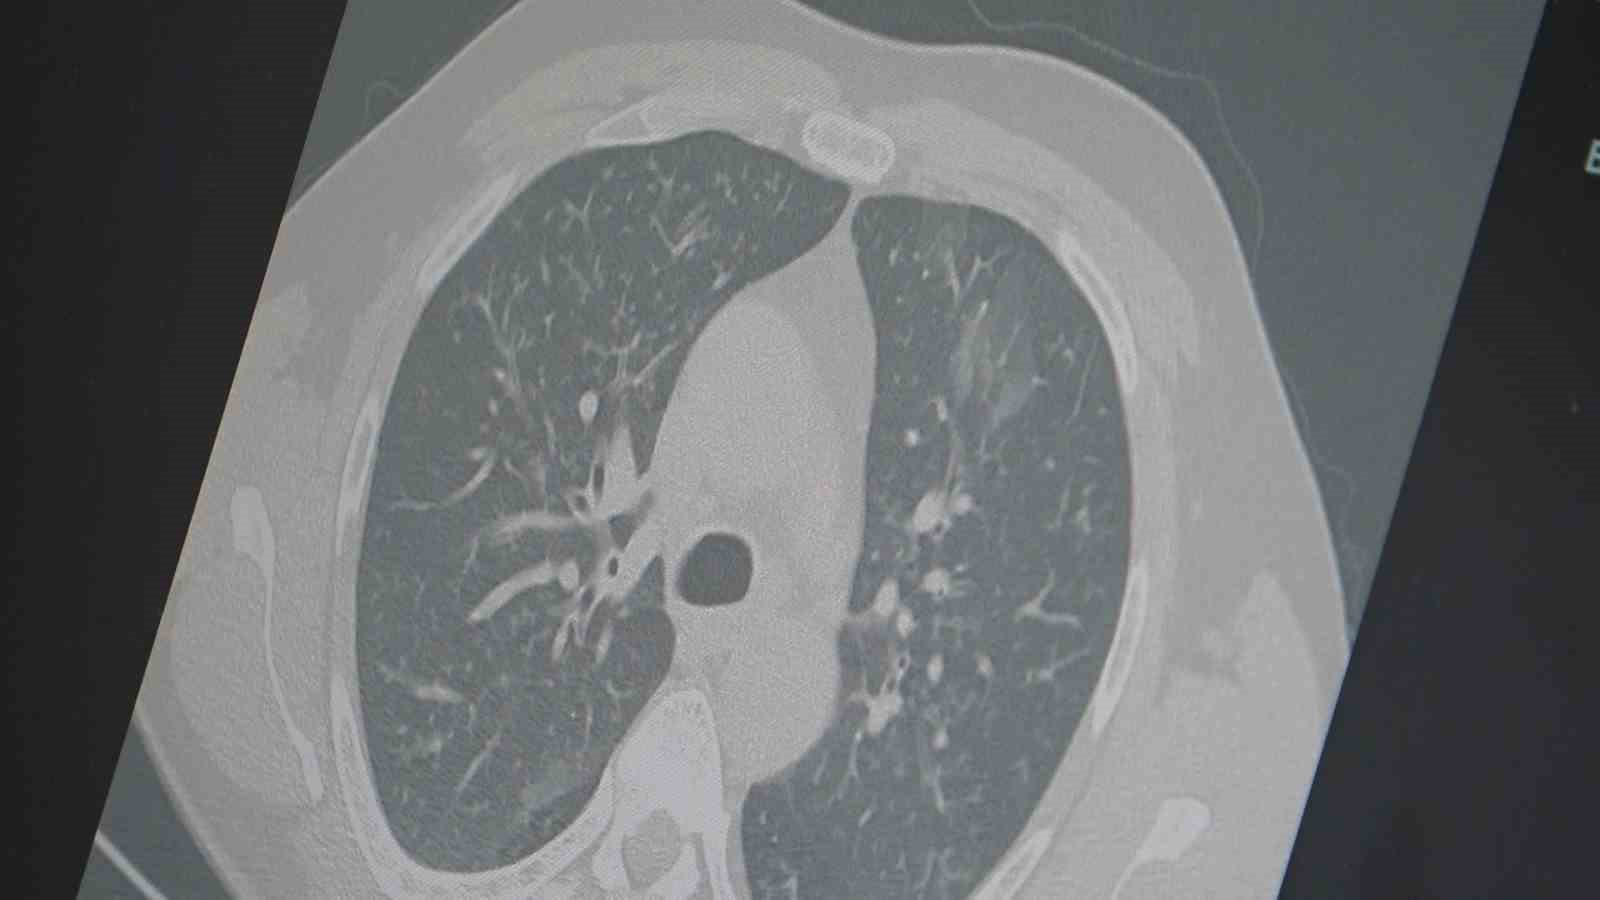

Dr. Özkaya, grip ve Kovid-19’un zatürreye dönüşme potansiyelinin bulunduğunu belirterek, bu durumun özellikle akciğerlerde komplikasyonlara yol açabileceğini vurguladı.

Salgının hastaneye yatış oranlarındaki artışa da neden olduğunu ifade eden uzman, özellikle uzun süren öksürük ve nefes darlığı yaşayan kişilerin vakit kaybetmeden sağlık kuruluşlarına başvurmaları gerektiğini önerdi. Akciğer sağlığını korumak ve olası komplikasyonları önlemek için erken tanının önemine dikkat çekti.

Vatandaşlara yönelik uyarılarda bulunan Prof. Dr. Özkaya, grip benzeri şikayetleri olan kişilerin evlerinde dinlenmelerini tavsiye etti. Uzun süreli öksürük ve nefes darlığı çekenlerin derhal doktora başvurarak akciğer röntgeni çektirmeleri gerektiğini belirtti.